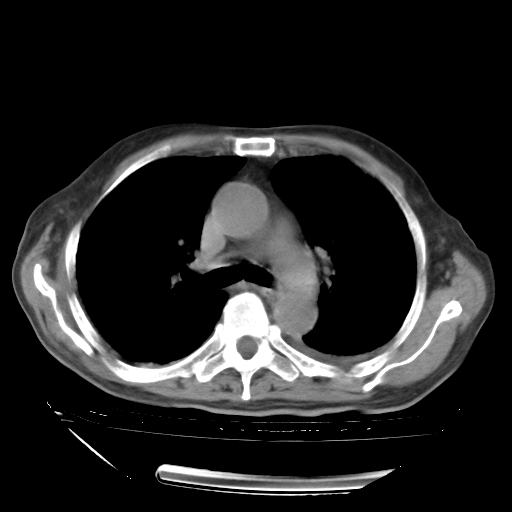

经过24天治疗,岳父的病情基本稳定。生活基本可以自理,可以下床活动。呼吸困难早已消失。体温基本正常。

只是甲强龙用80mg时血小板升到正常,改为60mg后又降到63×10*9/L。

主要治疗甲强龙80mg×14天,60mg×10天;同时抗结核(异烟肼+利福平+乙胺丁醇)。环磷酰胺0.1 tid 10天。

特别感谢胡教授、高管、桃子版主给出关键的治疗建议。桃版把所有肺部影像和全部临床资料请所在医院呼吸科、感染病科、结核科、临床免疫科专家会诊。临床免疫科专家制定了完整的治疗方案。